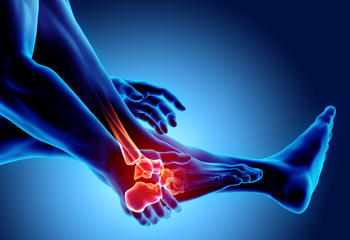

Arthritis Can Cause Pain in the Feet and Ankles

Understanding What Arthritis in the Feet Feels Like

Arthritis in the feet is a condition that can bring a range of discomforts and unique sensations. It often manifests as pain and stiffness in the joints, making every step a potential challenge. Individuals with foot arthritis may experience a deep, aching pain that worsens with movement. This discomfort can be present in various areas of the foot, including the toes, the midfoot, or the ankle. One common sensation associated with foot arthritis is a feeling of stiffness or inflexibility. It can be particularly pronounced in the morning or after periods of inactivity. As arthritis progresses, swelling and warmth may accompany the pain, making the affected foot feel tender to the touch. In more advanced cases, individuals may notice a grinding or popping sensation in the affected joints, indicating the wear and tear of the cartilage. Understanding what arthritis in the feet feels like is essential for timely diagnosis and effective management. If you have any of the above symptoms which may indicate arthritis in the feet, it is suggested that you schedule an appointment with a podiatrist who can guide you toward relief methods.

Arthritic Foot Care

Arthritis is a joint disorder that involves the inflammation of different joints in your body, such as those in your feet. Arthritis is often caused by a degenerative joint disease and causes mild to severe pain in all affected areas. In addition to this, swelling and stiffness in the affected joints can also be a common symptom of arthritis.